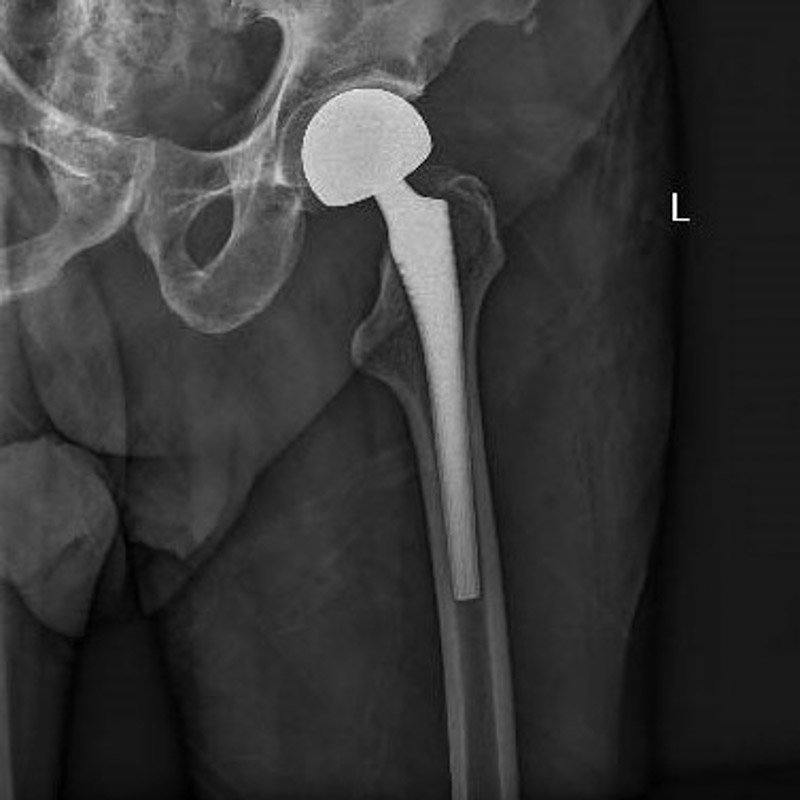

經過周密的術前準備,6月30日,在麻醉科團隊成功實施腰椎管內麻醉后,創傷骨科團隊為患者進行左側人工股骨頭置換術,手術過程順利。術后羅老伯恢復良好,圍術期內無心肌缺血癥狀發作,監測心電圖無動態改變。